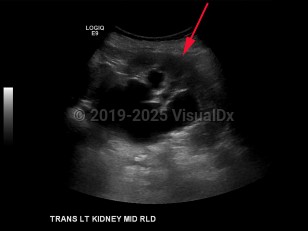

Hydronephrosis in Child

In children, hydronephrosis is most often secondary to an anatomic abnormality such as posterior urethral valves, vesicoureteral reflux, or ureteropelvic junction (UPJ) obstruction. Congenital anomalies account for a higher incidence of hydronephrosis in children compared to adults.

The Society for Fetal Urology (SFU) has developed a grading system for the severity of hydronephrosis. Severity ranges from grade 0 (mild; no renal pelvis dilation) to grade 4 (severe; dilation of the renal pelvis and calyces and thinning of the renal parenchyma).